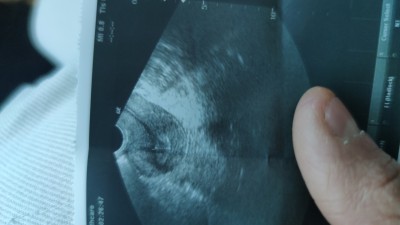

Doktora gittim sağ yumurtan yumusrtlamis hamilelik testi istedi

bu ne demek yardımcı olur musunuz  elime bu resmi verdi alttan muayene etti

Her ay bir tarafdaki yumurtlaiktan yumurta yetisiyor ve catliyor,sizin de bu ay sagdan catlamis,dr da dollenip dollenmediyi icin test istemis sizden,adetiniz kecmise ve ya gununuz yakinsa varsa cikar,benimde gecen ay sagdan catlmisdi ama gebelik olusmadi,simdi ovulyasyon testiyle takib ediyorum

Çatlamış demedi ama yumurtan yumurtlamis dedi o yüzden kafam karıştı